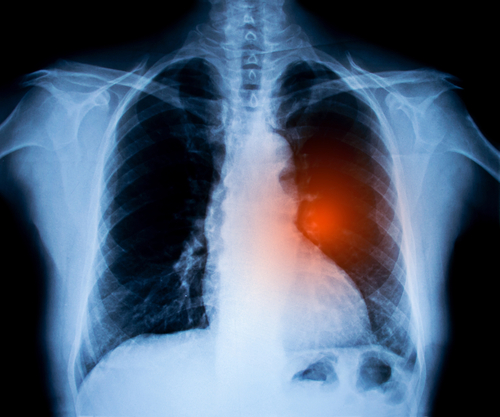

Nécessité d’un dépistage précoce

En revanche, la mortalité précoce à 3 mois est toujours importante et évolue peu par rapport à celle des deux cohortes précédentes, avec une augmentation modeste de la survie à 3 mois de 4,4 % (p=0,0001) en 20 ans. Le Dr Debieuvre relie cette relative stabilité au fait que la majorité des patients (60 %) sont diagnostiqués au stade métastatique, non ou peu curable, et ainsi non traités.

Le dépistage demeure un élément majeur en termes de survie. On constate que le stade TNM est toujours extrêmement déterminant du pronostic à 2 ans : mortalité à 2 ans de 10,6 % au stade I, 20,5 % au stade II, 40,4 % au stade III et 68,4 % au stade IV, stade auquel la survie est 3 fois moins importante qu’au stade I (31,6 % contre 89,4 %).